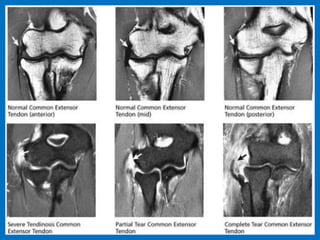

Lateral epicondylitis, commonly known as tennis

elbow, is a painful condition involving the tendons that

attach to the bone on the outside (lateral) part of the

elbow. Tendons anchor the muscle to bone. The muscle

involved in this condition, the extensor carpi radialis

brevis, helps to extend and stabilize the wrist. With

lateral epicondylitis, there is degeneration of the

tendon’s attachment, weakening the anchor site and

placing greater stress on the area. This can then lead to

pain associated with activities in which this muscle is

active, such as lifting, gripping, and/or grasping. Sports

such as tennis are commonly associated with this, but

the problem can occur with many different types of

activities, athletic and otherwise. 90% non tennis player.

Lateral epicondylitis.

Partial tear. Complete tear.

Tennis elbow.